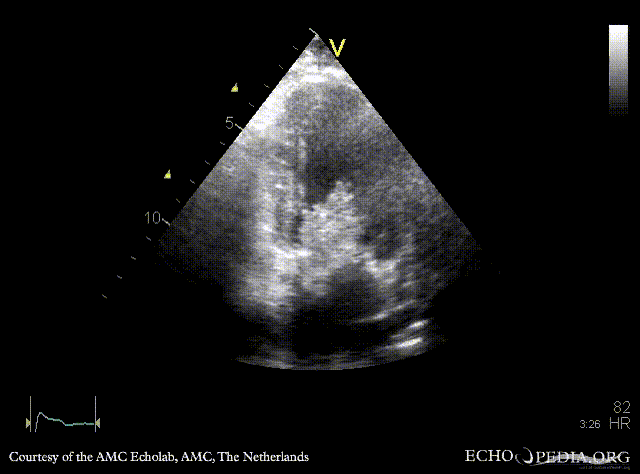

Giant myxoma in left atrium

A2CH

Subcostal view